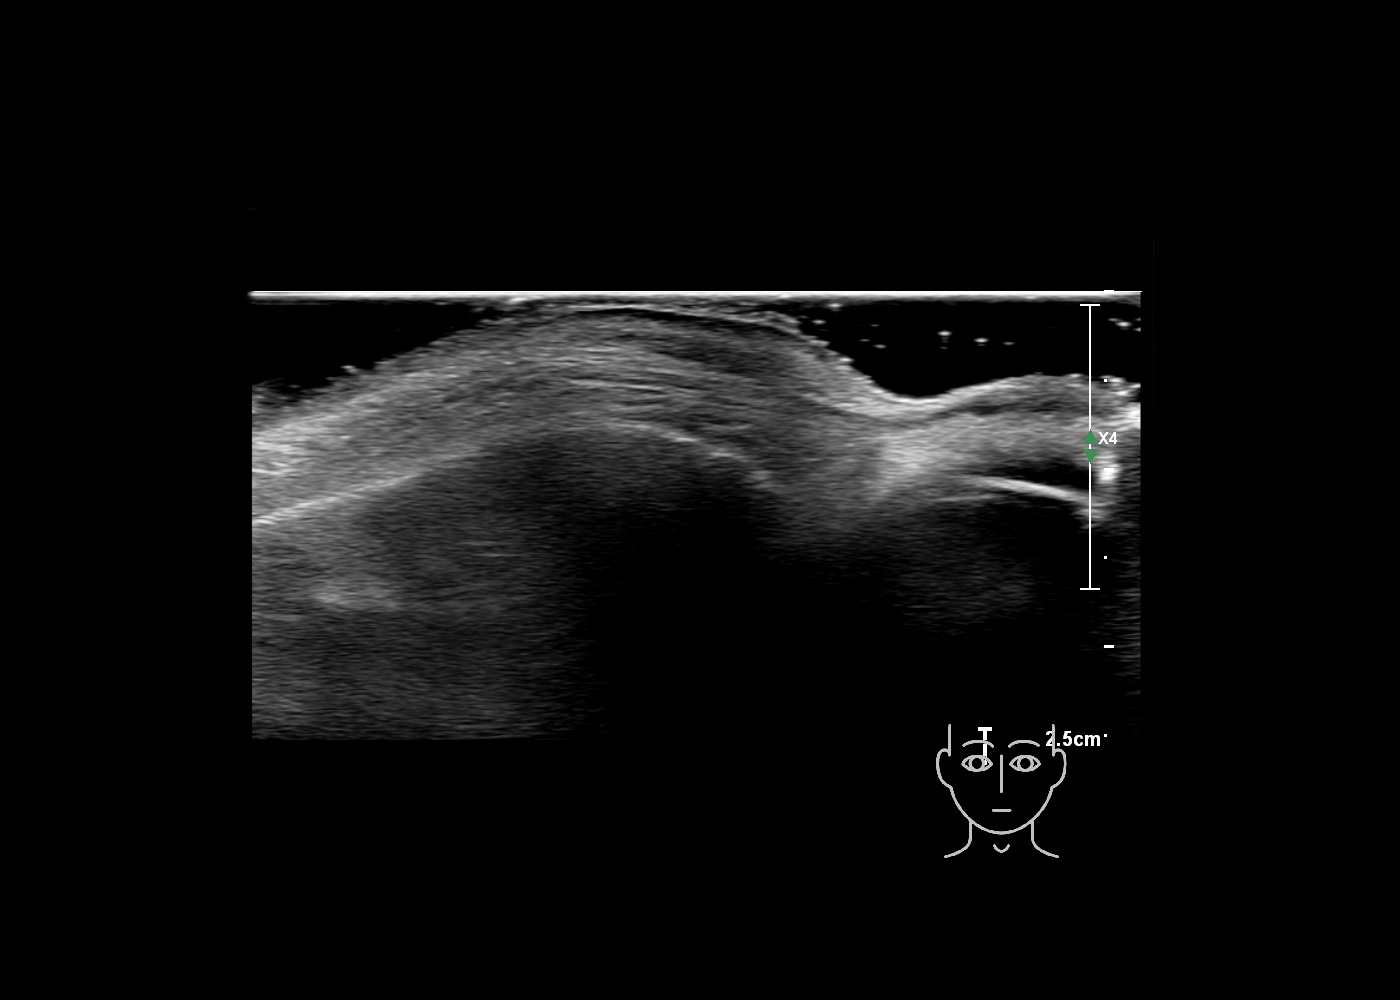

In this section you will learn more about the different layers of the face with the use of ultrasound. When you click on the secondary ultrasound image, you will see the different structures as an overlay. This will help to train yourself to recognize the different layers of the face.

Study the first image to recognize the different layers. If you are sure about the layers, swipe to the second image to view the answer (if applicable).